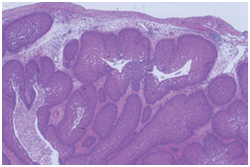

Histopathological statutes: The squamous epithelium displays finger like projections, the epithelial maturation pattern is orderly with epithelial hyperkeratosis. Spinous epithelial cells may depict cytoplasmic vacuolation with pale, clear perinuclear haloes, nuclear pyknosis and infrequent basilar hyperplasia. Oral squamous papillomas frequently display koilocytosis on account of the co-existent cytopathic influence. Atypical nuclear alterations may be exemplified; particularly with immune-compromised (HIV positive) individuals.9 The epithelium displays a typical maturation pattern with prominent hyperkeratosis. Epithelial to basal cell quantification is moderate (basilar hyperplasia) along with an extensive koilocytic transition.1 Virally induced carcinomas are the poorly differentiated, non-keratinizing tumours and may be enunciated in the tonsils of sexually active young men. Majority of the tumours elucidate the p16 proteins. Oro-pharyngeal cancers which are reactive for human papilloma virus (HPV) frequently depict basaloid morphology. Apart from a viral genesis, squamous papillomas may ensue from mechanical irritation or may be genetically determined as a constituent of Cowden’s syndrome.

Figure 4 Papillomatous lesions with a prominent fibro-vascular core.

Figure 5 Inverted Papilloma with epithelial hyperplasia.